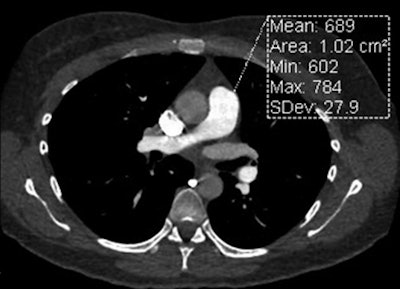

High-pitch acquisition using data collected from each array during one-quarter of the gantry yields high temporal resolution of 75 msec. This technique combined with ECG synchronization -- not used in conventional CTPA -- offers rapid imaging of data at a specified phase of the cardiac cycle and at very low radiation doses, the group noted.

High-pitch CTPA showed higher signal intensity for the pulmonary arteries, and image quality scores demonstrated the technique's superiority for the assessment of cardiovascular structures (p < 0.001), particularly the ability to minimize motion in the central pulmonary arteries (p < 0.001) and deliver greater pulmonary enhancement (p = 0.001). And high pitch did all of this using a significantly lower radiation dose: a mean 2.9 ± 1.4 mSv for high-pitch scanning versus 6.1 ± 2.9 mSv (p < 0.001) for conventional CTPA.